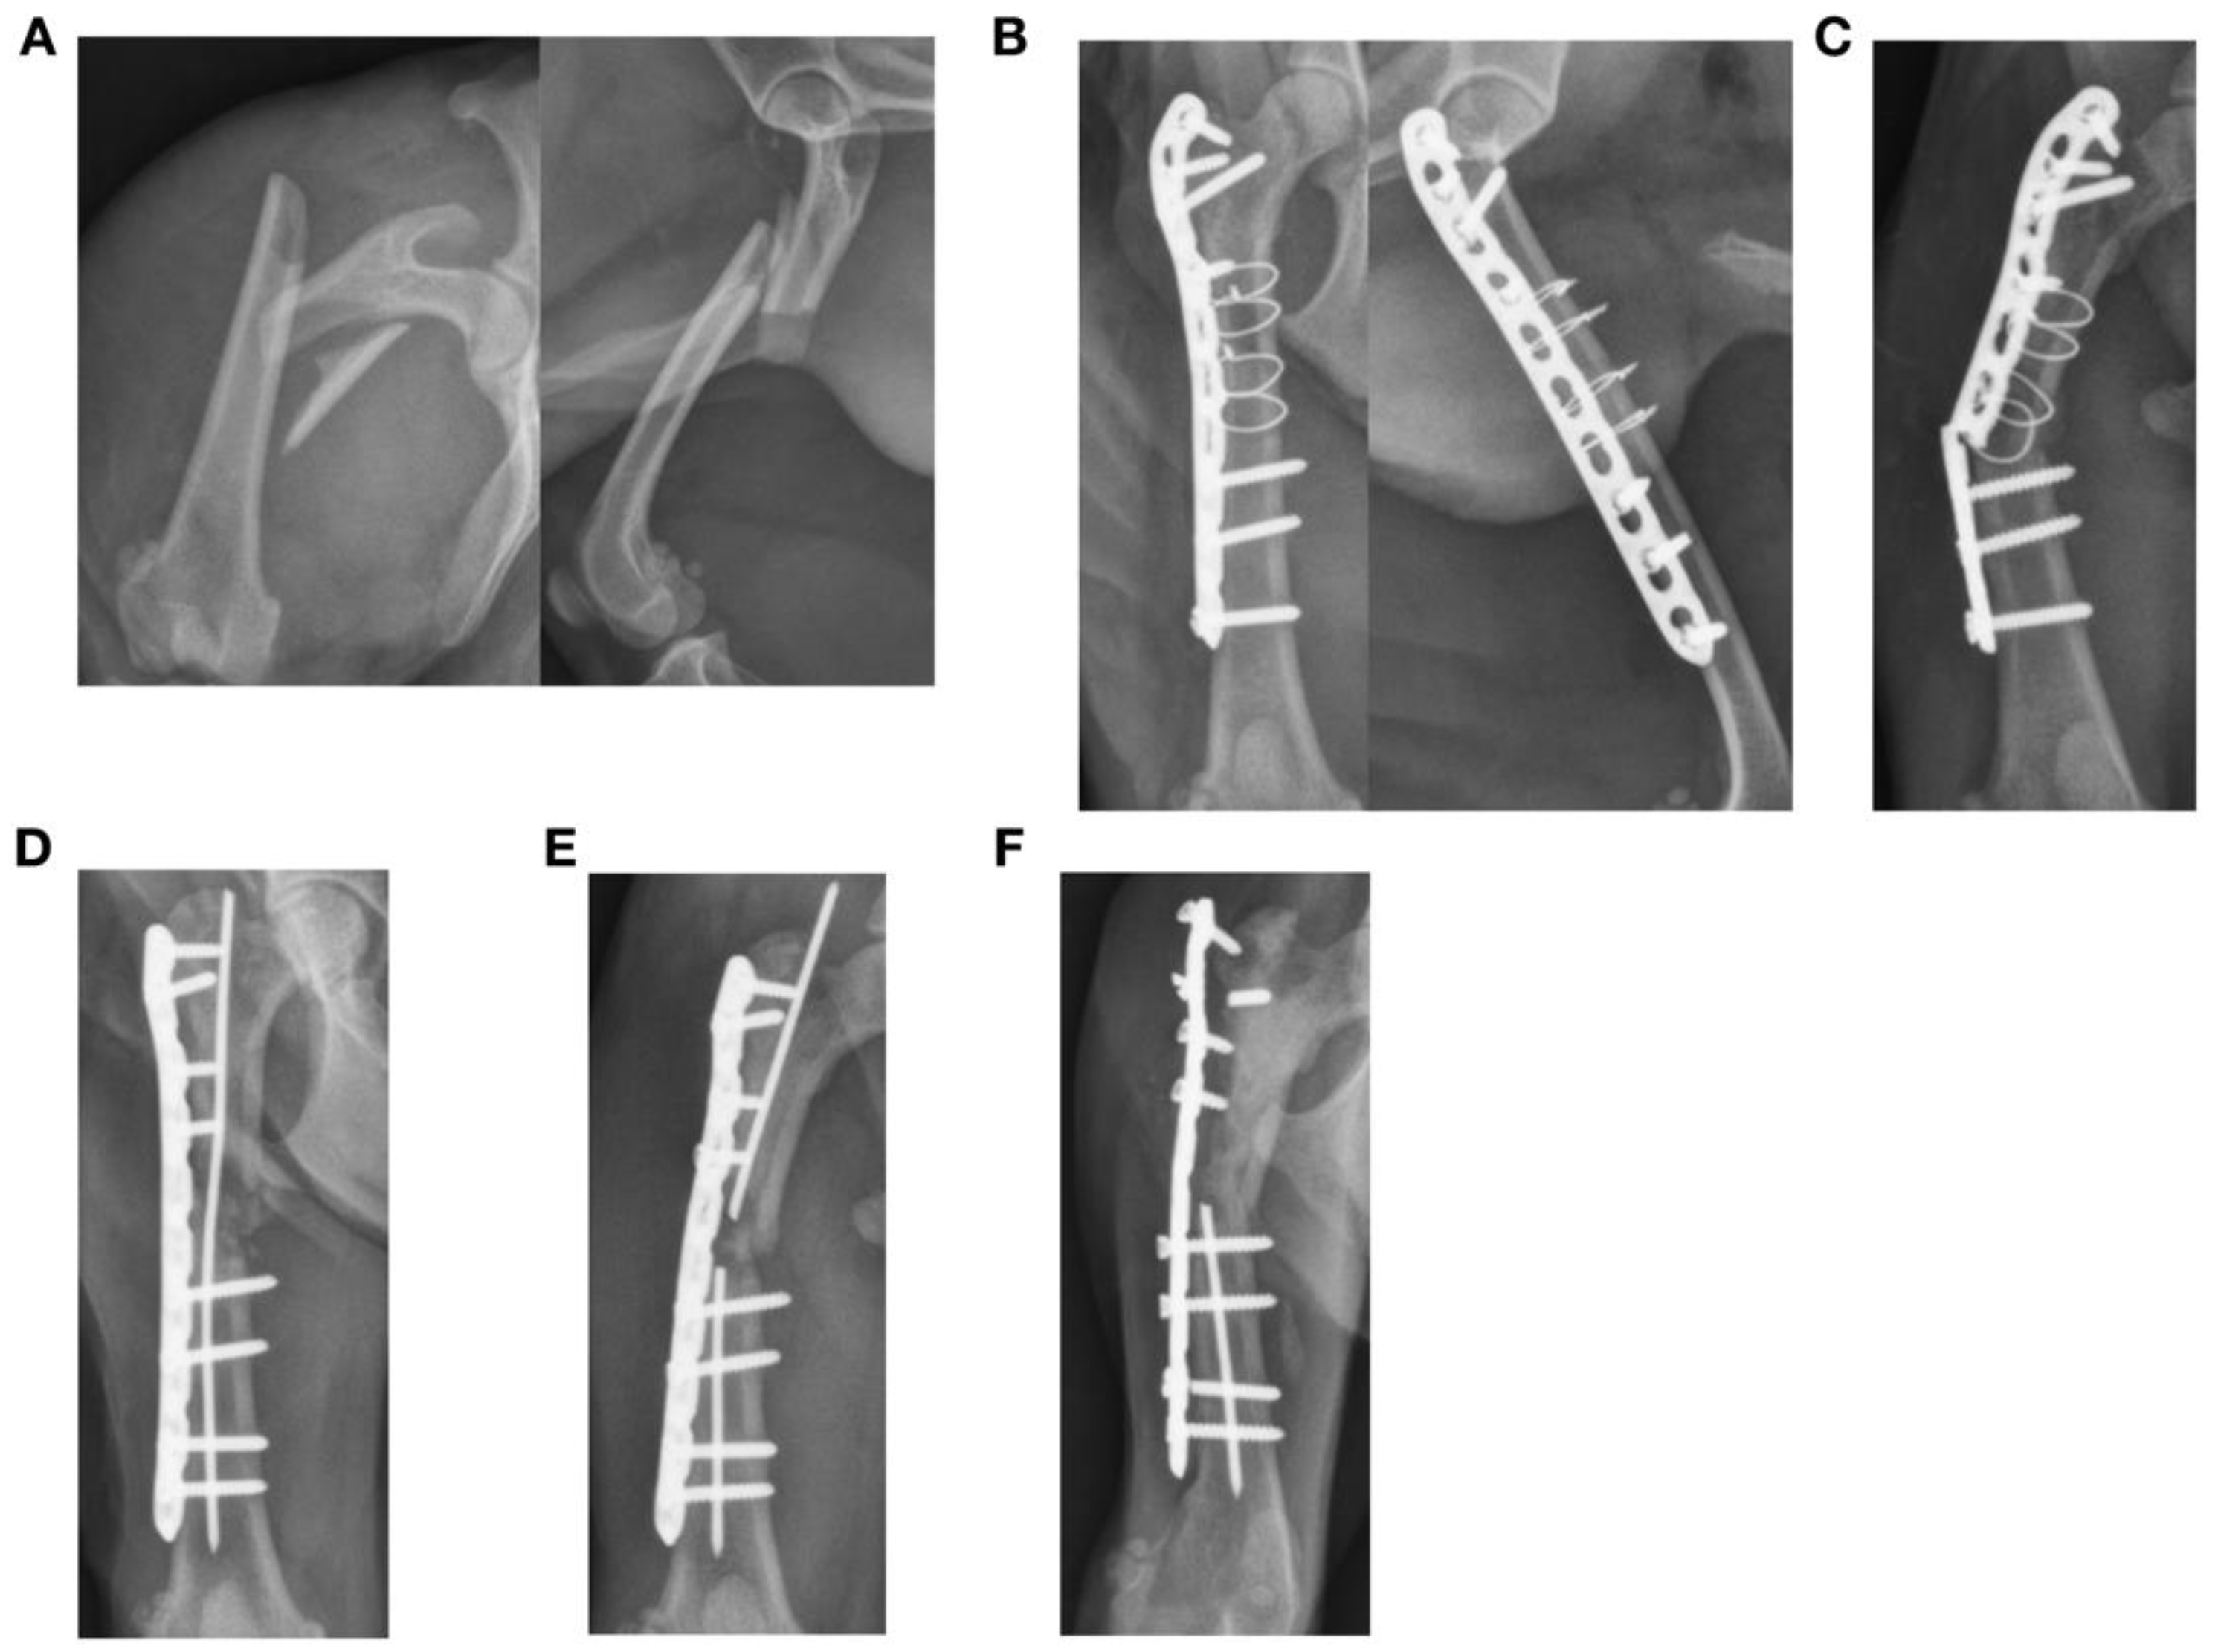

3.3. Plate Failure (11 Fractures)

| 18 | N | Femur | Diaphyseal | Y | N | 11 | 6 | 6 | 0.55 | 83.2 | 4.7 | 72.9 | 3.5 mm LCP | 32.94 | Lateral |

| 19 | Y | Ilium | Shaft | N | Y | 7 | 8 (cranial) | 6 (caudal) | 1.00 | 59.9 | 25.9 | 8.1 | 2.0 mm DCP | 0.42 | Lateral |

| 20 | Y | Acetabulum | Caudal | Y | Y | 6 | 6 (cranial) | 6 (caudal) | 1.00 | 32.1 | 46.0 | 6.7 | 2.7 mm SOP | n/a | Lateral |